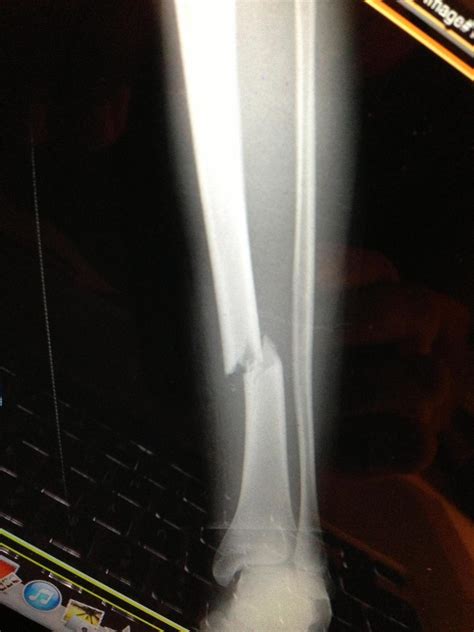

Diagnosis of Tibial and Fibular Fractures

Diagnosing tibial and fibular fractures typically involves a combination of physical examination and imaging tests. The diagnostic process may include:

• X-Rays: Standard X-rays to visualize the bones and determine the location and severity of the fracture.